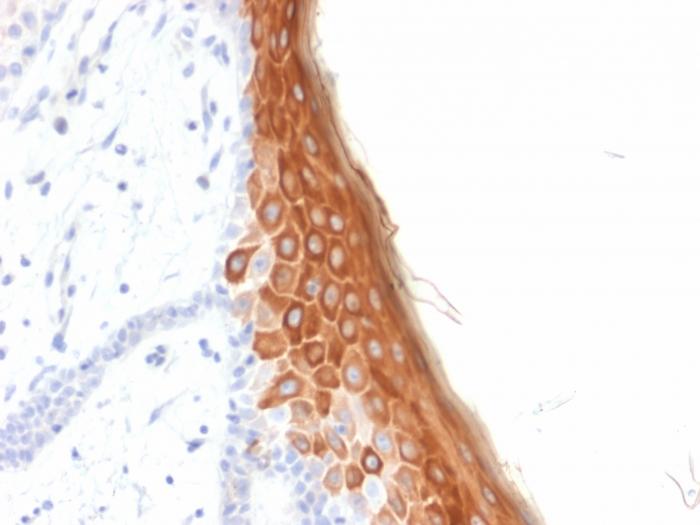

This MAb recognizes a protein of 56.5 kDa, identified as cytokeratin 10 (CK10). CK10 is expressed in all suprabasal layers of the epidermis. In the epidermis, expression of CK10 strictly parallels the extent of differentiation; it is absent in the basal layer, appears in the first suprabasal layers and increases in concentration towards the granular layer. However, CK10 is rarely detected in early stages of vulvar squamous carcinomas (tumors less than 2 cm, clinical stage I) regardless of the tumor grade. In larger and more advanced tumors (greater than 2 cm, clinical stages II and III), CK10 is detected very frequently. Expression of CK10 is related to maturation of malignant keratinocytes, being preferentially detected in more-differentiated parts.Primary antibodies are available purified, or with a selection of fluorescent CF® Dyes and other labels. CF® Dyes offer exceptional brightness and photostability. Note: Conjugates of blue fluorescent dyes like CF®405S and CF®405M are not recommended for detecting low abundance targets, because blue dyes have lower fluorescence and can give higher non-specific background than other dye colors.

Positive Control

A431, HeLa, MCF7 cells. Esophagus or tonsil.

Antibody target cellular localization

Cytoskeleton

Cell tissue expression

Epidermal cells